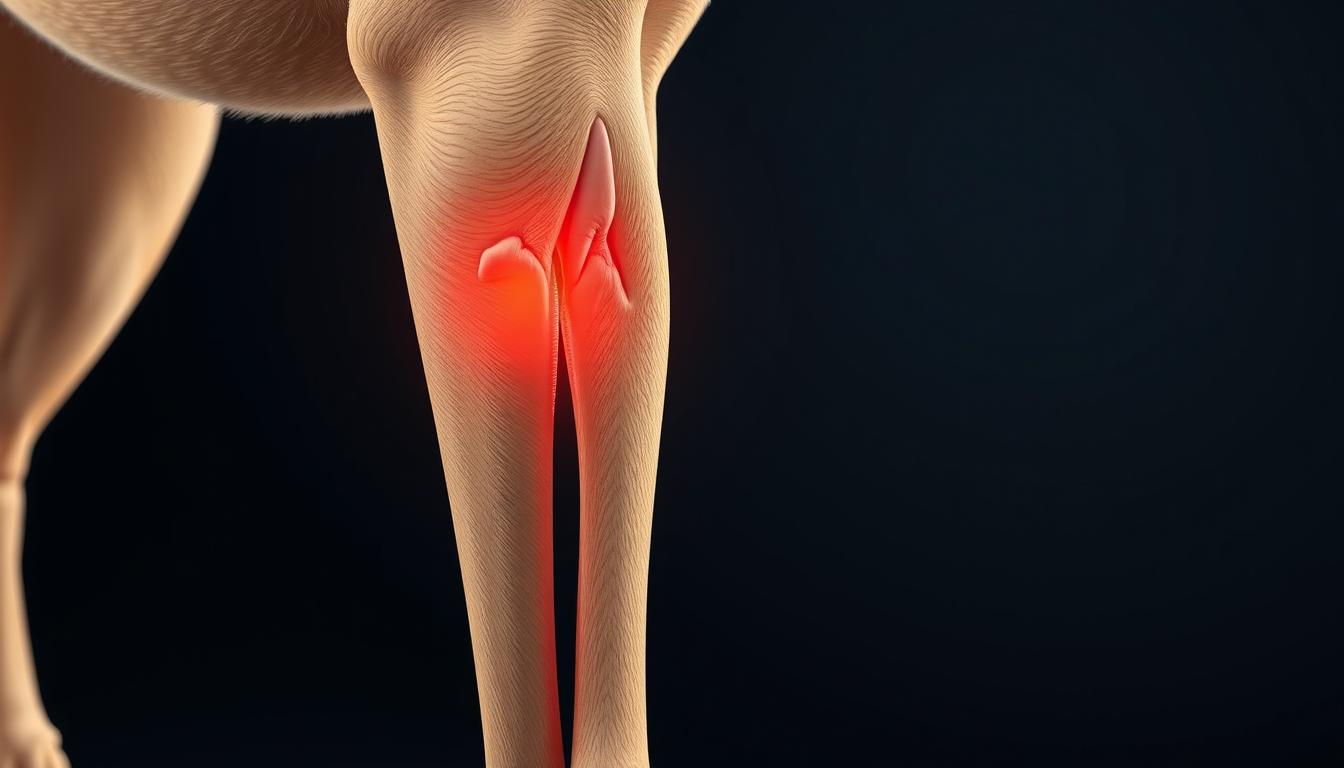

Tenosinovita reprezintă inflamația tecii care ansamblează tendonul. Aceasta face parte din categoria afecțiunilor musculo-scheletale identificate la câini. Se manifestă prin inflamația tecii tendoane, determinând durere accentuată și umflături vizibile în regiunea afectată.

Se distinge de condiții similare, precum tendinita, prin faptul că vizează teaca tendonului, nu pe tendon în sine. Este esențial să înțelegem această diferențiere. Doar așa ne putem orienta corespunzător către tratament adecvat și măsurile preventive adaptate pentru câinele impactat.

Recunoașterea simptomelor tenosinovitei la câine este esențială pentru a putea oferi tratamentul potrivit cât mai devreme. Simptome comune se manifestă prin șchiopătare, sensibilitate crescută la nivelul membrelor și prezența unor umflături vizibile. Câinele va arăta durere prin rigiditate atunci când se mișcă și ar putea evita activitățile zilnice obișnuite.

Semnele tenosinovitei variază în funcție de gravitatea și de localizarea inflamației. În cazuri ușoare, câinele poate arăta doar o ușoară șchiopătare. Pe de altă parte, în formele severe, poate refuza să-și folosească membrul afectat.